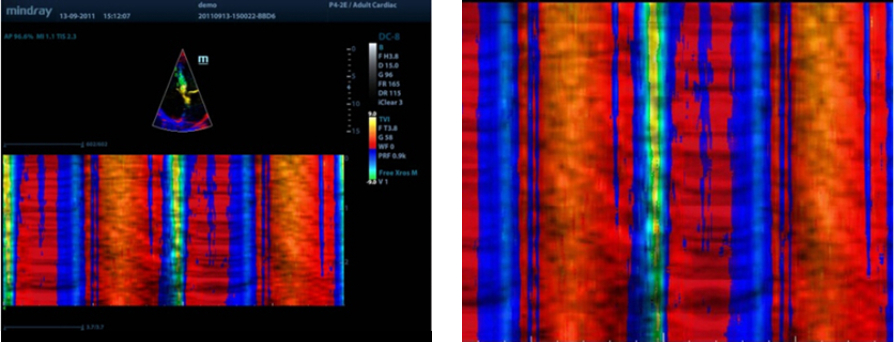

Free Xros M?

Gain precise anatomical observation by freely placing sample lines at any angle. Attain better images through simultaneous display of up to 3 sample lines.

Free Xros CM?

Accurately evaluate myocardial motion at different phases, and simultaneously determine myocardial synchronisation. The high frame-rate provides accurate results.

TDI

Tissue Doppler Imaging allows you to quantitatively evaluate local myocardial movement and function, providing complete TDI modes for faster and direct diagnoses.